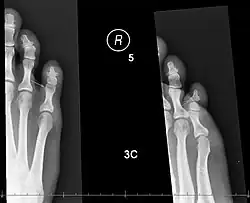

X-rays of fractures of the proximal (left) and distal (right) phalanges in the little toe. | |